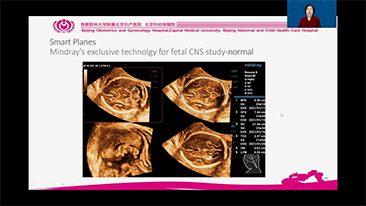

Los flujos de trabajo de OBG optimizados son necesarios para admitir grandes cantidades de pacientes para las visitas de evaluaciĂłn de la salud de las mujeres. Por ejemplo, las malformaciones del sistema nervioso central (SNC) son una de las anomalĂas congĂ©nitas mĂĄs comunes. Debido a las diversas condiciones del diagnĂłstico por imĂĄgenes, como una posiciĂłn fetal deficiente, el plano sagital medio (MSP) es particularmente difĂcil de obtener a partir de una ecografĂa 2D. Por lo tanto, la detecciĂłn y las mediciones automatizadas pueden mejorar en gran medida la eficiencia de la exploraciĂłn.